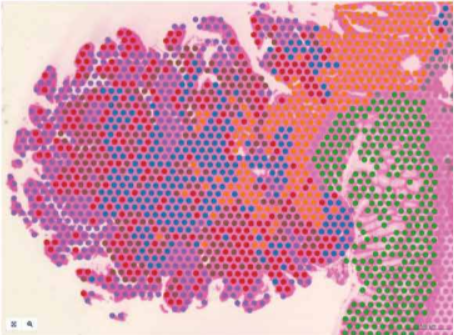

此次发布的 VisiumHD 芯片摒弃了以大直径 55um 的 spot 设计,而是采用 2 *2um 的正方形当做基础分析单位,芯片中间没有空隙。真正的能够做到无间隙,无偏好性的单细胞分辨率水平的空间转录组。目前 HD 芯片发布捕获框大小是 6.5*6.5mm 的规格,可检测物种是人和小鼠,兼容石蜡样本。

▲Visium HD 空间基因表达玻片包含两个 6.5 x 6.5 mm 的捕获区

▲Visium HD 空间基因表达玻片的捕获区含有约 1100 万个 2 x 2 µm 连续区块,实现单细胞水平的空间分辨率。

▲全转录组、单细胞分辨率、连续覆盖